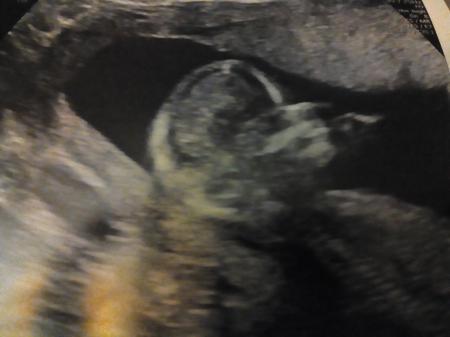

...war heute die Aussage vom Spezialisten, dass alles in bester Ordnung zu sein scheint. Wir waren heute bei der NFM. Eine dreiviertel Stunde hat er geschallt und wir konnten alles auf einem großen Flachbildschirm an der Wand mitverfolgen. Mein Mann war richtig ergriffen, immerhin durfte er zum ersten Mal beim Ultraschall dabei sein. Und das Baby so in Aktion zu sehen ist ja deutlich was anderes, als ein US-Bild in der Hand zu halten. Das Baby hatte wieder seinen eigenen Willen - wenn der Arzt messen wollte, hat es richtig doll gezappelt oder sich ganz weggedreht. Nach ca. der Hälfte hat es herzhaft gegähnt (das hat der Arzt sogar vergrößert und noch mal in Zeitlupe gezeigt) und ist dann wohl eingeschlafen. Da hat der Arzt es mächtig ärgern müssen, damit es wieder aufwacht und mitmacht. Gehirn, Herz, Nieren, Magen, Blase und alle möglichen Körperteile sind gut entwickelt und es ist heute bei 13+1 schon 7,9 cm groß. Bei der Frage nach dem Geschlecht sagte der Arzt, dass er es erst ab 14+ sagen darf, alles andere wäre gesetzlich verboten. Zum Abschluss meinte er aber plötzlich: "Jetzt hat sie sich wieder zusammengerollt." Zuvor hat er immer nur von "es" gesprochen. Mein Mann hat es zwar nicht mitgekriegt, aber ich bin mir sicher, mich nicht verhört zu haben. Vielleicht erfahren wir ja nächste Woche beim normalen Termin bei meinem FA genaueres. Ich wünsche euch allen einen schönen Valentinsabend!

Bild zu Das schönste Valentinstagsgeschenk... - Forum für August - Mamis

Was ein schönes Ergebnis und ein süßes Bild Toll, dass alles in Ordnung ist!

Toll und so ein süßes Bildchen von deinem Mäuschen!